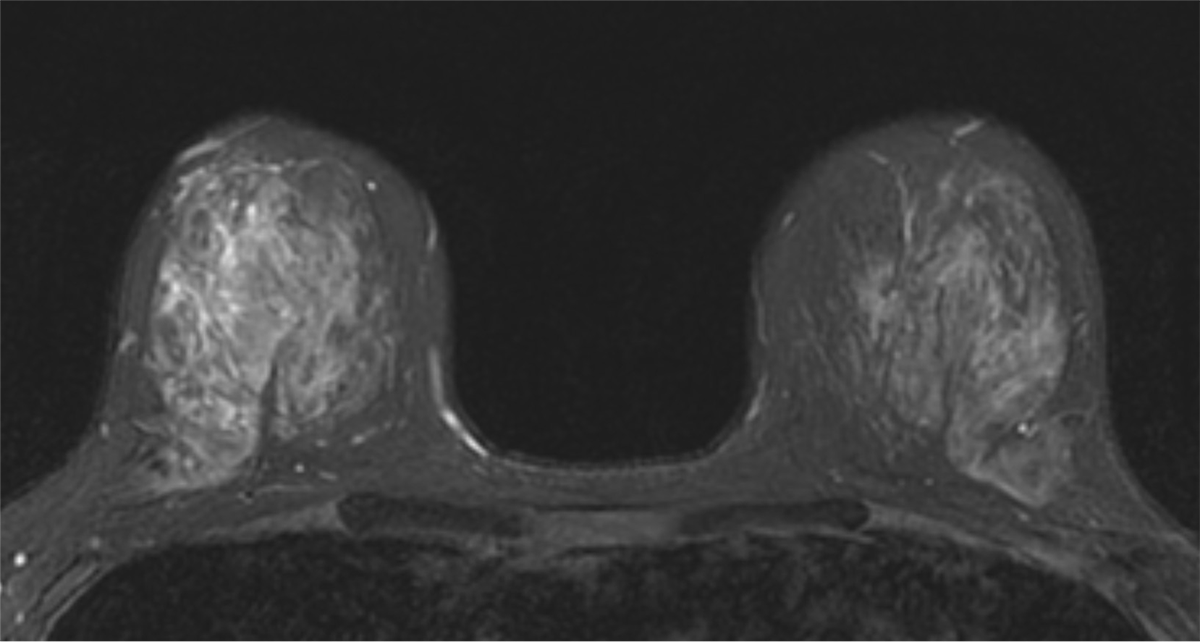

40歳代、女性、非浸潤性乳管癌 ductal carcinoma in situ (DCIS)

右乳腺AC-C区域を中心に複数の低エコー域を認めた。針生検でDCISと診断され手術加療の方針となり、術前広がり診断目的でMRI撮像した。

症例解説

40歳代女性。201X年より超音波検査で低エコー領域として描出される両側乳腺症に対してフォローアップされていた。初回より12年後のフォローアップで、右乳腺C区域からAC区域に広がる低エコー域に血流シグナルを認め悪性の可能性が示唆された。

針生検の結果、ductal carcinoma in situ (DCIS)が疑われた。手術加療の方針となり、術前の広がり評価目的に造影MRIを撮像した。乳房全切除術及びセンチネルリンパ節生検を施行し、最終病理診断はDCISであった。

当該疾患の診断における造影MRIの役割

乳腺MRIは乳癌の広がりを高精度に診断できる。この症例においてもマンモグラフィーでは病変を指摘出来なかったが、MRIでは病変が明瞭に描出され、エコーで捉えられる領域よりも広範に及んでいる事が示された。3D解析を用いることでより俯瞰的な評価ができ、術式の選択や切除範囲の一助となった。